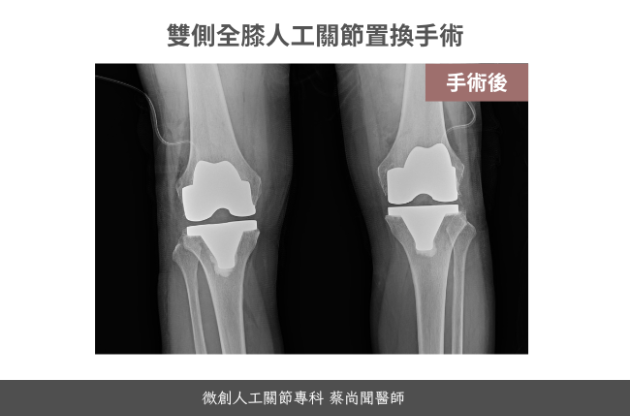

黃女士84歲

她是一位很認真的病患,事先做了很多功課,還辛苦跑了門診兩次為了當面再次會談確認手術細節,80多歲的年紀,整體身體狀況保持得很好,相當健康活

同時置換雙側人工膝關節的好處,在於不用經歷兩個恢復期的疼痛,然而在手術後的早期,也就是六周內,需要特別注意安全,小心不要跌倒扭到拐到受傷